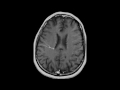

Developmental Venous Anomaly

This is a case of an incidentally detected developmental venous anomaly, or DVA, on a follow-up brain MR for an arachnoid cyst in a 38-year-old female. The first two images demonstrate the linear hypointense lesion coursing through the deep and periventricular white matter of the right frontoparietal region on the susceptibility weighted sequences. The third image, which is a T2-weighted sequence, demonstrates a corresponding linear T2 hyperintense signal at the DVA. The fourth and fifth images demonstrate the DVA on post contrast T1-weighted sequences with linear enhancement and extension towards the subependymal veins on the right. Two middy dilated subependymal veins are demonstrated on the right on the final postcontrast image. A DVA results from a network of dilated medullary veins radially converging on a large vein that drains into deep or superficial veins. A DVA is surrounded by normal brain parenchyma. DVAs are thought to arrise from prenatal occlusion of a vein draining into the deep or superficial venous system. This results in a large collateral vein forming which drains through the white matter. Because the DVA represents a compensatory venous drainage pathway for normal brain, sacrifice of this pathway can result in venous infarction.